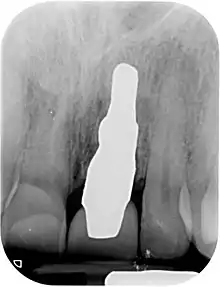

RAIs are custom made to perfectly fit the tooth socket of a specific patient immediately after tooth extraction. Therefore every implant is unique. As an optimized root-form it is much more than a simple 1:1 replica of a tooth. Since it exactly fills the gap left after the tooth is extracted, surgery is rarely needed. The implant can be produced from a copy of the extracted tooth, an impression of the tooth socket, or from a CT scan or CBCT scan.[3] The advantage of a CBCT scan is that the implant can be produced before extraction. With the former methods, it takes one or two days to fabricate an implant.

A root analogue implant can be fabricated from zirconium dioxide (zirconia) or titanium. Successful titanium RAIs have been three-dimensionally printed as porous one-piece implants, using CAD software.[4] However, zirconia is the preferred material, because it is more esthetic in color, with no grey discoloration visible through gums.[5][1]

- Natural form: a custom milled anatomic implant replicates the natural form of a tooth, so it simply fits into the tooth socket. Like the original tooth, a root analogue implant can have single- and multi-rooted forms.

- Esthetic: a ceramic RAI closely resembles a natural tooth in color. Thus there is no discoloration through the gums, as is commonly seen with titanium implants.